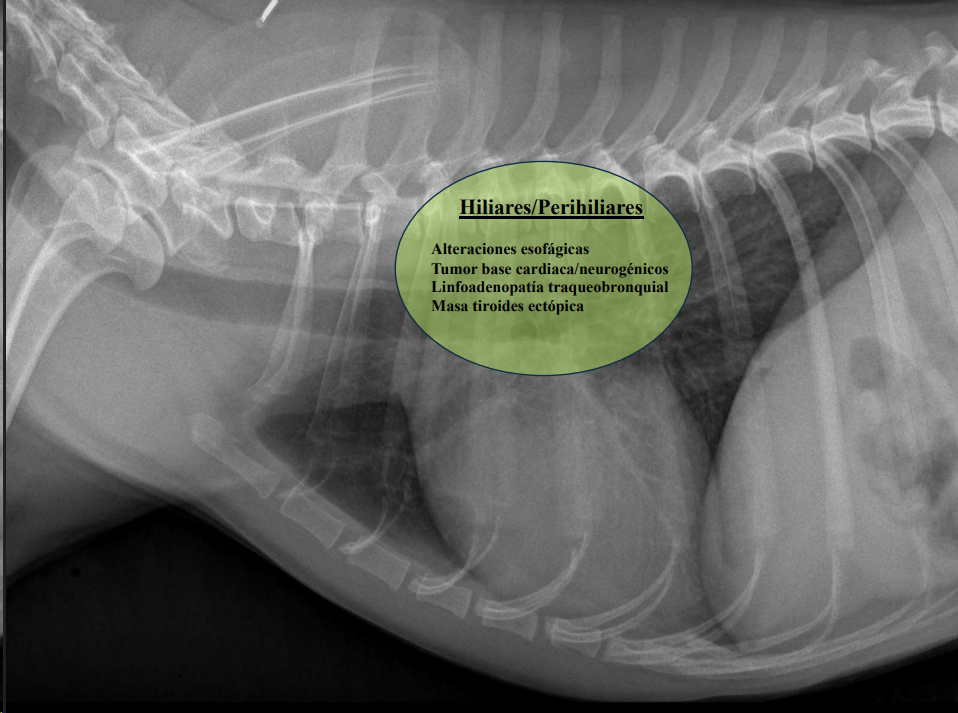

CLASIFICACIÓN DE MASAS MEDIASTÍNICAS

-

Craneodorsales: alteraciones esofágicas, aneurisma aórtico, hematoma, tumor base cardíaca/neurogénico, absceso, granuloma, lesión vertebral.

Desplazamiento traqueal ventral por neumoesofago

Desplazamiento traqueal dorsal por masa en el mediastino craneal

Hiliares/Perihiliares: alteraciones esofágicas, tumor base cardiaca, linfoadenopatía traqueobronquial, masa tiroidea ectópica.

Masa de opacidad tejido blando que desplaza la traquea y la bifurcación bronquial.

Puede ser por los nodulos parabronquiales, esofagico o por masa en el pulmón

Caudodorsales: hernia paraesofágica, tumores neurogénicos, granulomas.

Craneoventrales: linfoma, timoma, tumor tiroideo, histiocitosis, lipoma, fibrosarcoma, linfoadenopatía esternal o craneal, absceso, aneurisma auricular.